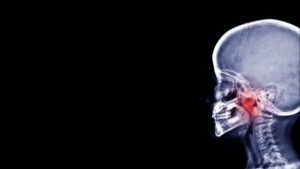

Adenoidectomy is the surgical removal of the adenoids – glands located above the mouth’s roof, behind the nose. In children, adenoids are an important part of the child’s immune system and protect against germs that may enter the body through the nose or mouth. Typically, these glands shrink and disappear by the teenage years. However,…

Adenoidectomy is a surgical procedure performed to remove adenoids that are chronically infected or swollen. When enlarged, adenoids can affect the flow of oxygen in the upper airway, from the nose to the larynx. In adults, swollen adenoids can cause obstructive sleep apnea, which is a serious medical condition that causes pauses in breathing during…

Adenoidectomy is surgery to remove the adenoids, which is tissue that is located behind the nasal passage. This is a very common procedure performed on children who have an underdeveloped immune system. The adenoids are part of the lymphatic system, and they help prevent bacteria and viruses from entering the body. Should bacteria and viruses…